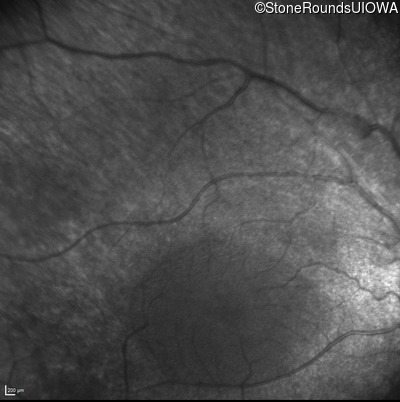

Infrared Fundus Photograph - Right - No Light Perception

Exemplar